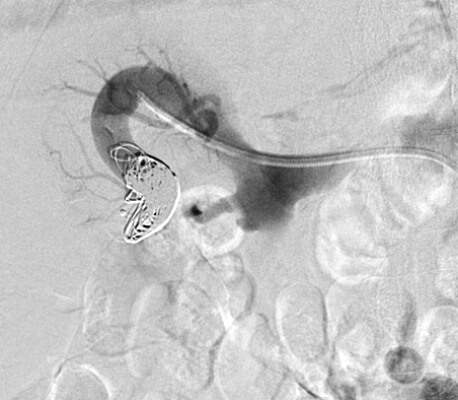

64 year old male who presents with right testicular pain, mild right flank pain, and signs of early CHF.

Comment: This patient presented with scrotal pain, right flank pain, and early CHF. Upon review of the imaging, it became clear that all three of these symptoms were related. The renal angiogram demonstrated prompt opacification of the right renal vein and IVC. This appeared to be secondary to an AV fistula that resulted in increased venous pressure, which contributed to the development of a varicocele (through a branch of the right renal vein draining into the right testicular vein before passing into the IVC). In addition, the outflow from the fistula likely increased right heart pressure, leading to his cardiac symptoms.